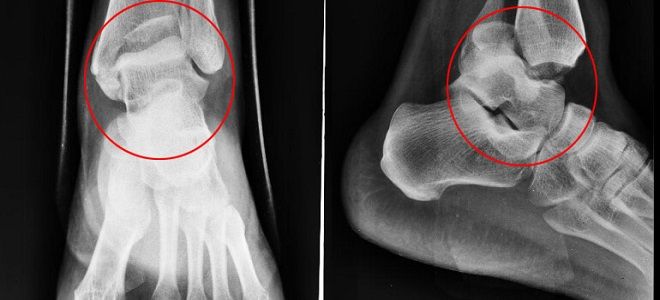

Рентген артроза голеностопного сустава

Эта методика занимает центральное место в процессе диагностики. Ее популярность объясняется легкостью доступа к рентгенологическим исследованиям. На рентгеновских снимках специалист имеет возможность проанализировать состояние суставной поверхности и костной ткани. В зависимости от выявленных изменений устанавливаются степени артроза голеностопного сустава. На основе степени изменений, а также объема и характера поражения, медицинские работники разрабатывают индивидуальные планы лечения.